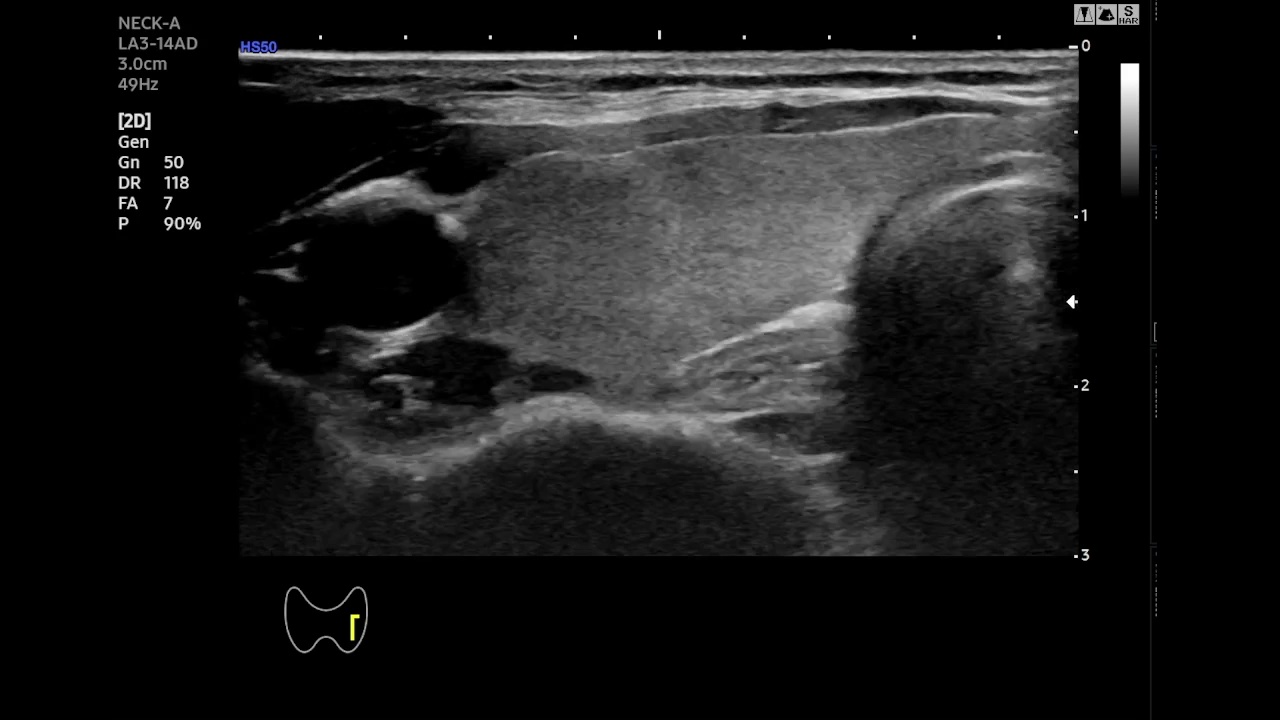

Qualitative Analysis of Temporal Stability- To better highlight the temporal behavior of SAM-2 and EMA-SAM, we visualize predictions at representative frames sampled from a complete RFA sequence. Figure 2 shows a three-row comparison: the first row displays the original ultrasound frames at selected timestamps (with ellipses indicating omitted intermediate frames), the second row shows SAM-2 predictions, and the third row presents EMA-SAM results. As the sequence progresses, SAM-2 occasionally loses the PTMC region when it becomes indistinct or is occluded by RFA bubbles, sometimes mis-segmenting nearby tissue. In contrast, EMA-SAM maintains a coherent segmentation trajectory throughout the sequence. Its confidence-weighted exponential-moving-average pointer preserves a robust latent prototype of the lesion, allowing rapid re-identification and boundary recovery once the PTMC reappears.

Original

SAM2

EMA-SAM